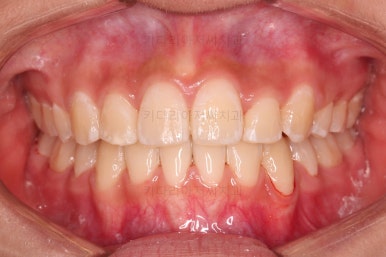

치료 종료시의 모습이에요.

총 21개월 걸렸고요.

발치를 중간에 결정했기 때문에 조금 지체된 면이 없지 않았으나 기간부터 치료 결과까지 만족스러운 치료였습니다.

동래교정치과의 전후 사진을 비교해 볼게요.

치여링 가지런해졌고, 교합과 중앙선 등 입안의 모습이 매우 좋아졌어요.

불규칙하게 마모되어 있던 치아의 개별 형태도 약간씩 다듬어 드렸고요.

입매도 본인이 원하는 정도로 만들었고, 웃는 모습, 뻐드러졌던 각도도 매우 잘 개선이 되었네요.

기울어보이던 치열의 경사도 개선이 되었고요.

전반적으로 만족스러운 치료였습니다.